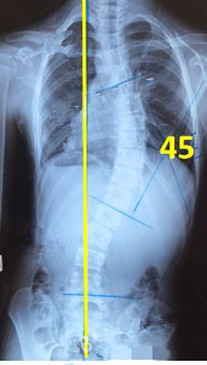

脊柱側彎矯形器(支具)是通過外力對側彎的脊柱進行矯正。所以,支具的力點位置及大小非常重要。當患者生長發(fā)育速度較快或支具矯正效果較好時,側彎矯正的進程也會較快,此時為了充分利用孩子生長階段的最佳矯正期,一定要對支具進行及時的調整和更換。

一般經過三個月至六個月的治療,對稱度都能得到改善,力線回正。

此時由于患者已經完全適應支具的力點,且體表變化較大,為了進一步矯正,我們需要對支具進行調整。如果由于孩子身高的變化較大,為了更進一步的矯正,可以考慮更換新的支具。

未穿支具